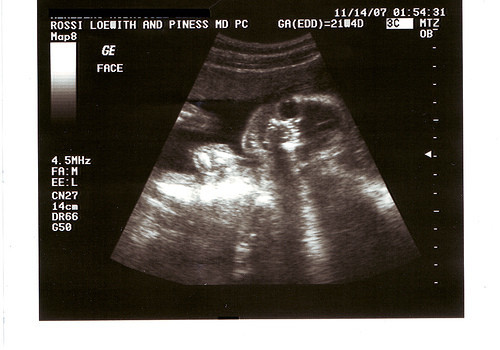

En concreto le practicaron ecografías en las semanas 12, 16, 20, 25, 29, 34 y 38 de su gestación dos facultativos diferentes y en ningún momento se les comunicó desviación alguna de la normalidad.

El bebé nació con malformaciones que afectan a ambos brazos. La pareja reclamó que “no llegó a haber diagnóstico prenatal de dicha malformación. Es decir, que a la usurpación del derecho de los padres a decidir si seguían adelante o no con el embarazo, se añade el enorme impacto psicológico tras el parto”, explicó el abogado Ignacio Martínez García.